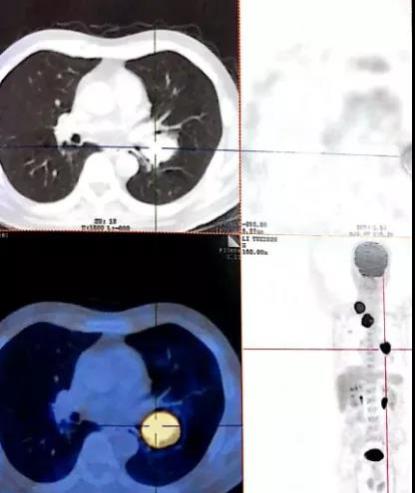

之后一直在当地的市人民医院行卡铂+信迪利单抗静滴方案化疗8个月余,虽然病情得到了一定的控制,但效果欠佳,为了寻求更好的治疗效果,行进一步针对性治疗,经多方打听后了解到广州中医药大学金沙洲医院肿瘤热疗中心有治疗肺癌方面的专家,治疗效果很显著,于今年3月份来到我院就诊。通过查体,胸部CT检查结果显示:慢性支气管炎症、肺气肿,双肺多发大泡;双肺多发斑片灶,肺部治疗病变后,右侧上颌实炎及右侧锁骨上多发淋巴结转移:双侧胸膜肥厚、粘连。

胡群峰教授结合患者既往病史、辅助检查结果,明确诊断为:肺恶性肿瘤(左下肺低分化非角化性鳞癌 T3N3MO IIIB期)。确定病症后,根据张大爷的实际病情胡教授制定了一套完整的治疗方案,治疗上继续予以抗肿瘤、营养支持,最后手术治疗清除病灶,行双侧支气管动脉造影、根据造影情况予灌注及栓塞治疗;达到减瘤控制肿瘤继续发展的效果。

制定好治疗方案后,胡群峰耐心的与患者及家属沟通病情及治疗方案,患者及家属表示理解并同意手术,签署知情同意书后,胡教授带领医护人员立马展开手术,为患者施行左支气管动脉造影+介入药物灌注+介入栓塞术后期再联合肿瘤热疗。

手术后CT

(与手术前CT的团状形肿瘤相对照,手术后CT肿瘤同一位置消失了)

手术室里,患者仰卧于DSA介入手术床上,心电监测生命体征正常,予常规消毒、常规铺巾,麻醉满意后胡教授凭借多年丰富的临床经验和精湛的技术带领医护团队有条不紊的开始手术。全程大约用了46分钟,最后手术顺利完成,患者体征正常,安全送回病房。目前,通过介入手术治疗后的张大爷已经得到很好的恢复,结束了8个月以来化疗的痛苦,重新走上了康复之路。